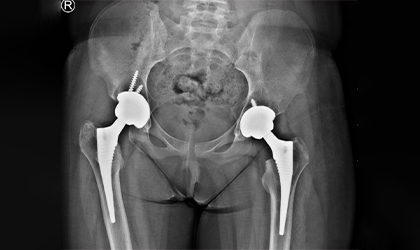

Rheumatoid Arthritis, Conquered

This 54 year old professor from a medical college was referred to us with severe damage to both hips